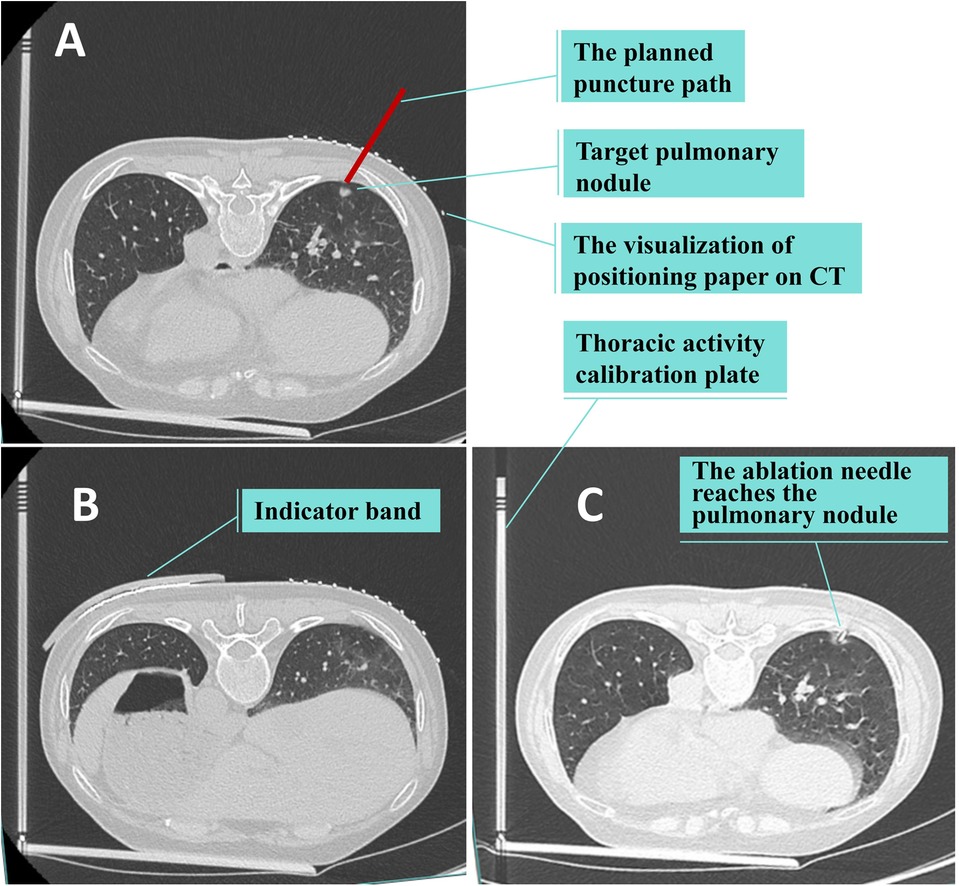

① Based on the location of the lung lesion, an appropriate body position is selected. The thoracic activity calibration plate is placed on the CT examination bed, with one side of it pressed between the chest and the bed surface, and the other side erected beside the thorax. Positioning paper (grid paper with lead wire) is affixed on the chest wall skin corresponding to the lung lesion, and the indicator band is attached on the side of the thorax with greater activity. The first CT scan is conducted to determine the puncture point, puncture level, and the scale of the thoracic activity calibration plate indicated by the attached indicator band on the chest skin (designated as “e”). The included angle between the intended needle insertion direction and the horizontal plane is measured (designated as “a” degrees), and the depth of the nodule from the skin is determined (designated as “b” centimeters). The positioning buckle is fastened at the “e” scale of the thoracic activity calibration plate, the laser is turned on, and the horizontal line corresponding to the “e” scale is projected. The patient is instructed to adjust the breathing amplitude to make the laser line coincide with the indicator band. At this time, the horizontal line (“c” line) corresponding to the puncture level and the intended puncture point are marked on the patient's skin according to the laser indication of the CT machine. ② The puncture needle is clamped on the laser angle guider and the laser on the guider is turned on. The guider is held and the puncture needle is inserted from the puncture point to beneath the skin. ③ The angle of the guider is adjusted to make the horizontal line of the laser coincide with the c line and to make the cross light of the laser parallel to the longitudinal and transverse axes of the CT bed respectively. ④ The angle of the guider is adjusted to make the XY axis (parallel to the patient's horizontal plane) displayed on the laser angle meter be the intended needle insertion angle, and the Z axis (parallel to the patient's sagittal plane) angle be 0 degrees. ⑤ The patient is once again instructed to adjust the breathing amplitude to make the laser line projected by the positioning buckle of the thoracic activity calibration plate coincide with the indicator band. The laser angle guider is pushed and the puncture needle is advanced to the predetermined depth, then the guider and the puncture needle are separated. ⑥ A CT scan is conducted again to determine whether the puncture needle has reached the predetermined position. ⑦ If the position of the puncture needle is not perfect as seen on CT, the puncture is retreated as per the situation, and the needle is reinserted under the guidance of the LAG until the puncture needle reaches the perfect position. ⑧ Once the position of the puncture needle is satisfactory, operations such as biopsy, ablation, or release of the positioning needle are initiated. ⑨ After the operation, CT is rechecked to determine whether there are complications such as hemopneumothorax and pulmonary hematoma. If the lung compression due to pneumothorax exceeds 30%, or if the hemothorax is expected to have more than 300 ml of pleural effusion, closed thoracic drainage is performed under CT positioning. See Figures 3, 4.

Figure 4. Ct scan. (A,B) The first CT scan is conducted to determine the puncture point, puncture level, and the scale of the thoracic activity calibration plate indicated by the attached indicator band on the chest skin. (C) The second CT scan is conducted again to determine whether the puncture needle has reached the predetermined position.